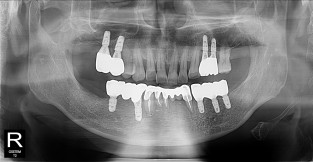

• 3

전체어금니

치료기간 : 2021-10-20 ~ 2023-08-31

1. 상기 x-ray 이미지 모두 동일한 해당 의료기관에서 진료한 환자입니다.

2. 상기 x-ray 이미지 모두 동일 인물의 것입니다.

3. 치료 전 이미지는 2021-10-20에 촬영했으며, 치료 후 이미지는 2023-08-31에 촬영하였습니다.

4. 상기 x-ray 이미지 모두 동일 조건에서 환자분의 동의를 받아촬영되었습니다.

* 임플란트 시술은 환자분의 상태(고혈압, 당뇨 등)에 따라 부작용이 있을 수 있으니, 반드시 전문의와 상담이 필요합니다.

* 임플란트 수술 부작용

: 수술 후 출혈, 교합, 통증, 붓기, 염증 등의 문제점이 발생할 수 있습니다.)